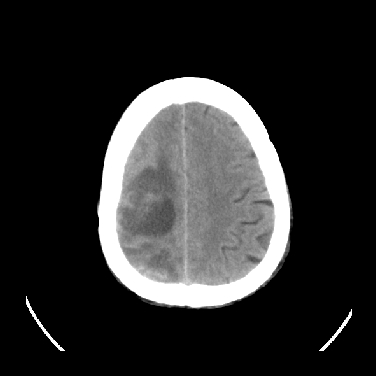

男,45岁,左侧肢体乏力1周。ex:胸片示:两肺团块状、斑片状密度增高影,其内可见小空洞。支纤镜、经皮肺穿示:干酪样物。

考虑右侧顶叶脑脓肿形成。

考虑右侧顶叶脑脓肿形成

结合病史考虑结核瘤,不除外转移瘤。

右侧顶叶脑脓肿!支持!

考虑右侧顶叶脑脓肿(结核性?)。

结核性脑脓肿可能大